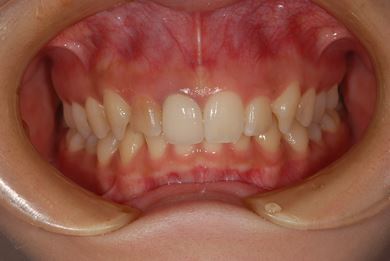

| 性別/年齢 | 女性 / 21歳 | ||||||||||||||||||||||||||||||||

| 主訴 | 歯の変色、欠けた部分を治したい。 | ||||||||||||||||||||||||||||||||

| 治療方針 | 上前歯を根管治療後、オールセラミッククラウンにて審美的回復を行う。 | ||||||||||||||||||||||||||||||||

| 治療内容 | オールセラミッククラウン2本(オールセラミック用土台2本) | ||||||||||||||||||||||||||||||||